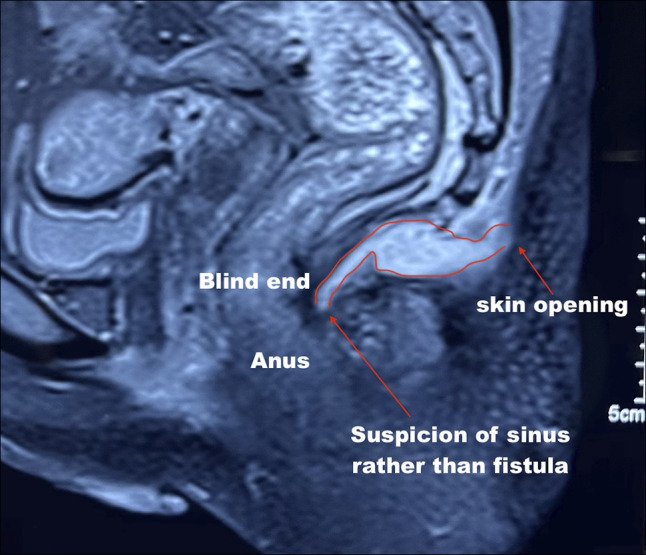

Abstract Image